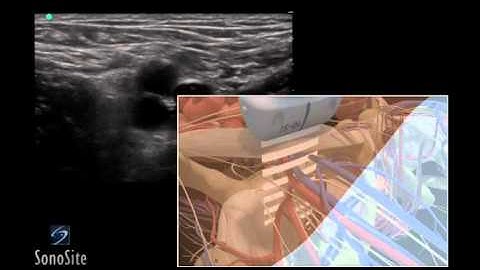

How To: Ultrasound Guided Insertion of a Subclavian Vein Catheter 3D Video